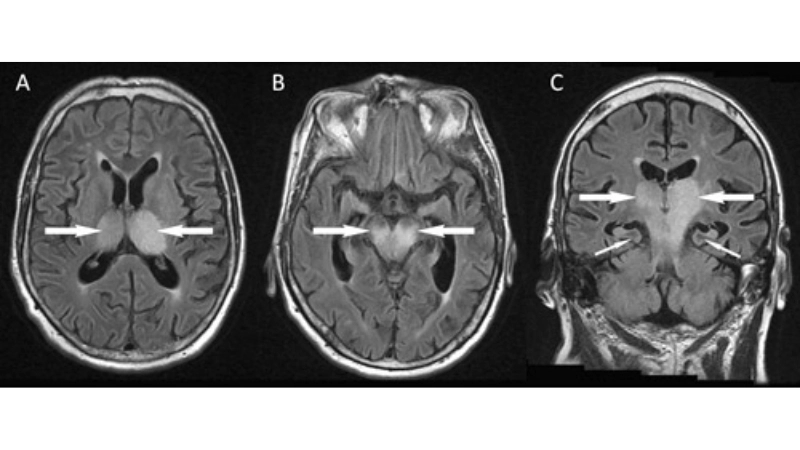

Image description of Murray Valley Encephalitis

Murray Valley Encephalitis is a rare but serious viral infection transmitted by mosquitoes, primarily affecting the brain and nervous system, with potential life-threatening complications.